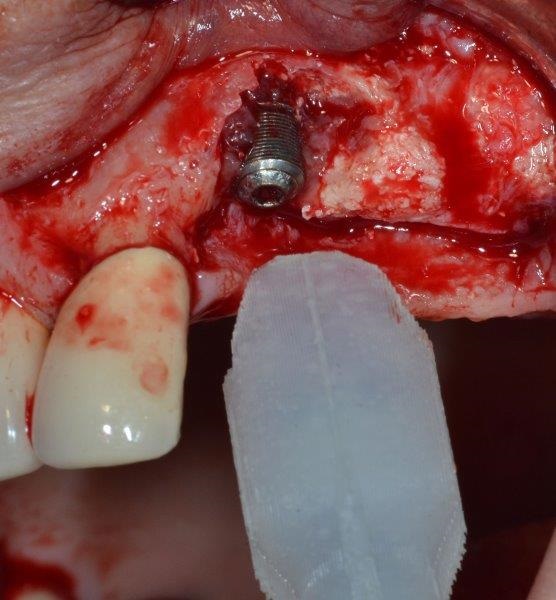

The ultrasonic cavitation device was placed onto the exposed part of the implant—there’s no need to create a tight seal between cavitation chamber and crestal bone—and the device was then activated (Fig. 10). A non-contact approach (without the metal tip contacting the implant) is advisable to avoid damaging the implant.

At the end of the decontamination process, a new sterile cover screw was positioned (Fig. 11).